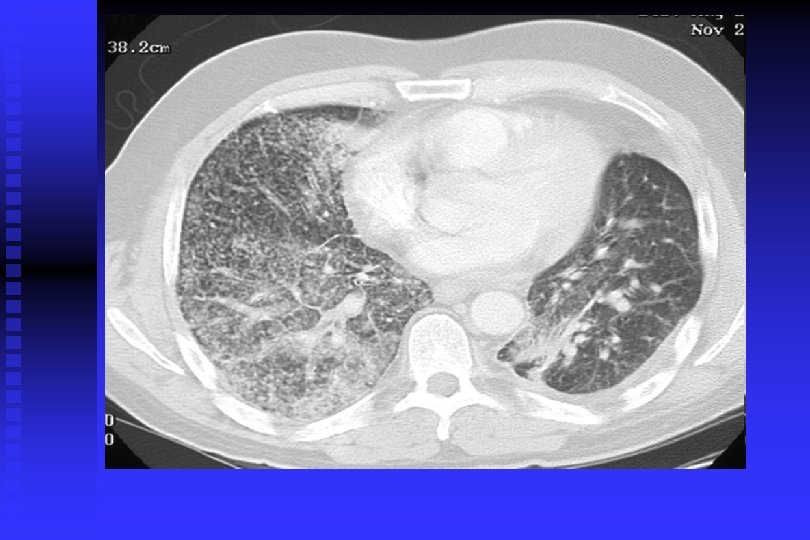

Cancer Pulmon

Cancer Pulmonar

DIAGNOSTICO DE CANCER PULMONAR RADIOGRAFIA DE TORAX: Permite descubrir CP en asintomáticos en 67 -82% y de estos el 24% tiene citología de esputo anormal. TOMOGRAFIA DE TORAX: Sensibilidad del 85% para CP y una especificidad del 95%. Per– mite descartar causas benignas de nódulos pulmonares con uni – dades Hounsfield >175= benigno; adenopatías <1 cm= benignos; 1 -2 cm= Indeterminado, >2 cm= positivo. Permite conocer actividad metastásica, y para estadificación (S= 73% y E= 80%).